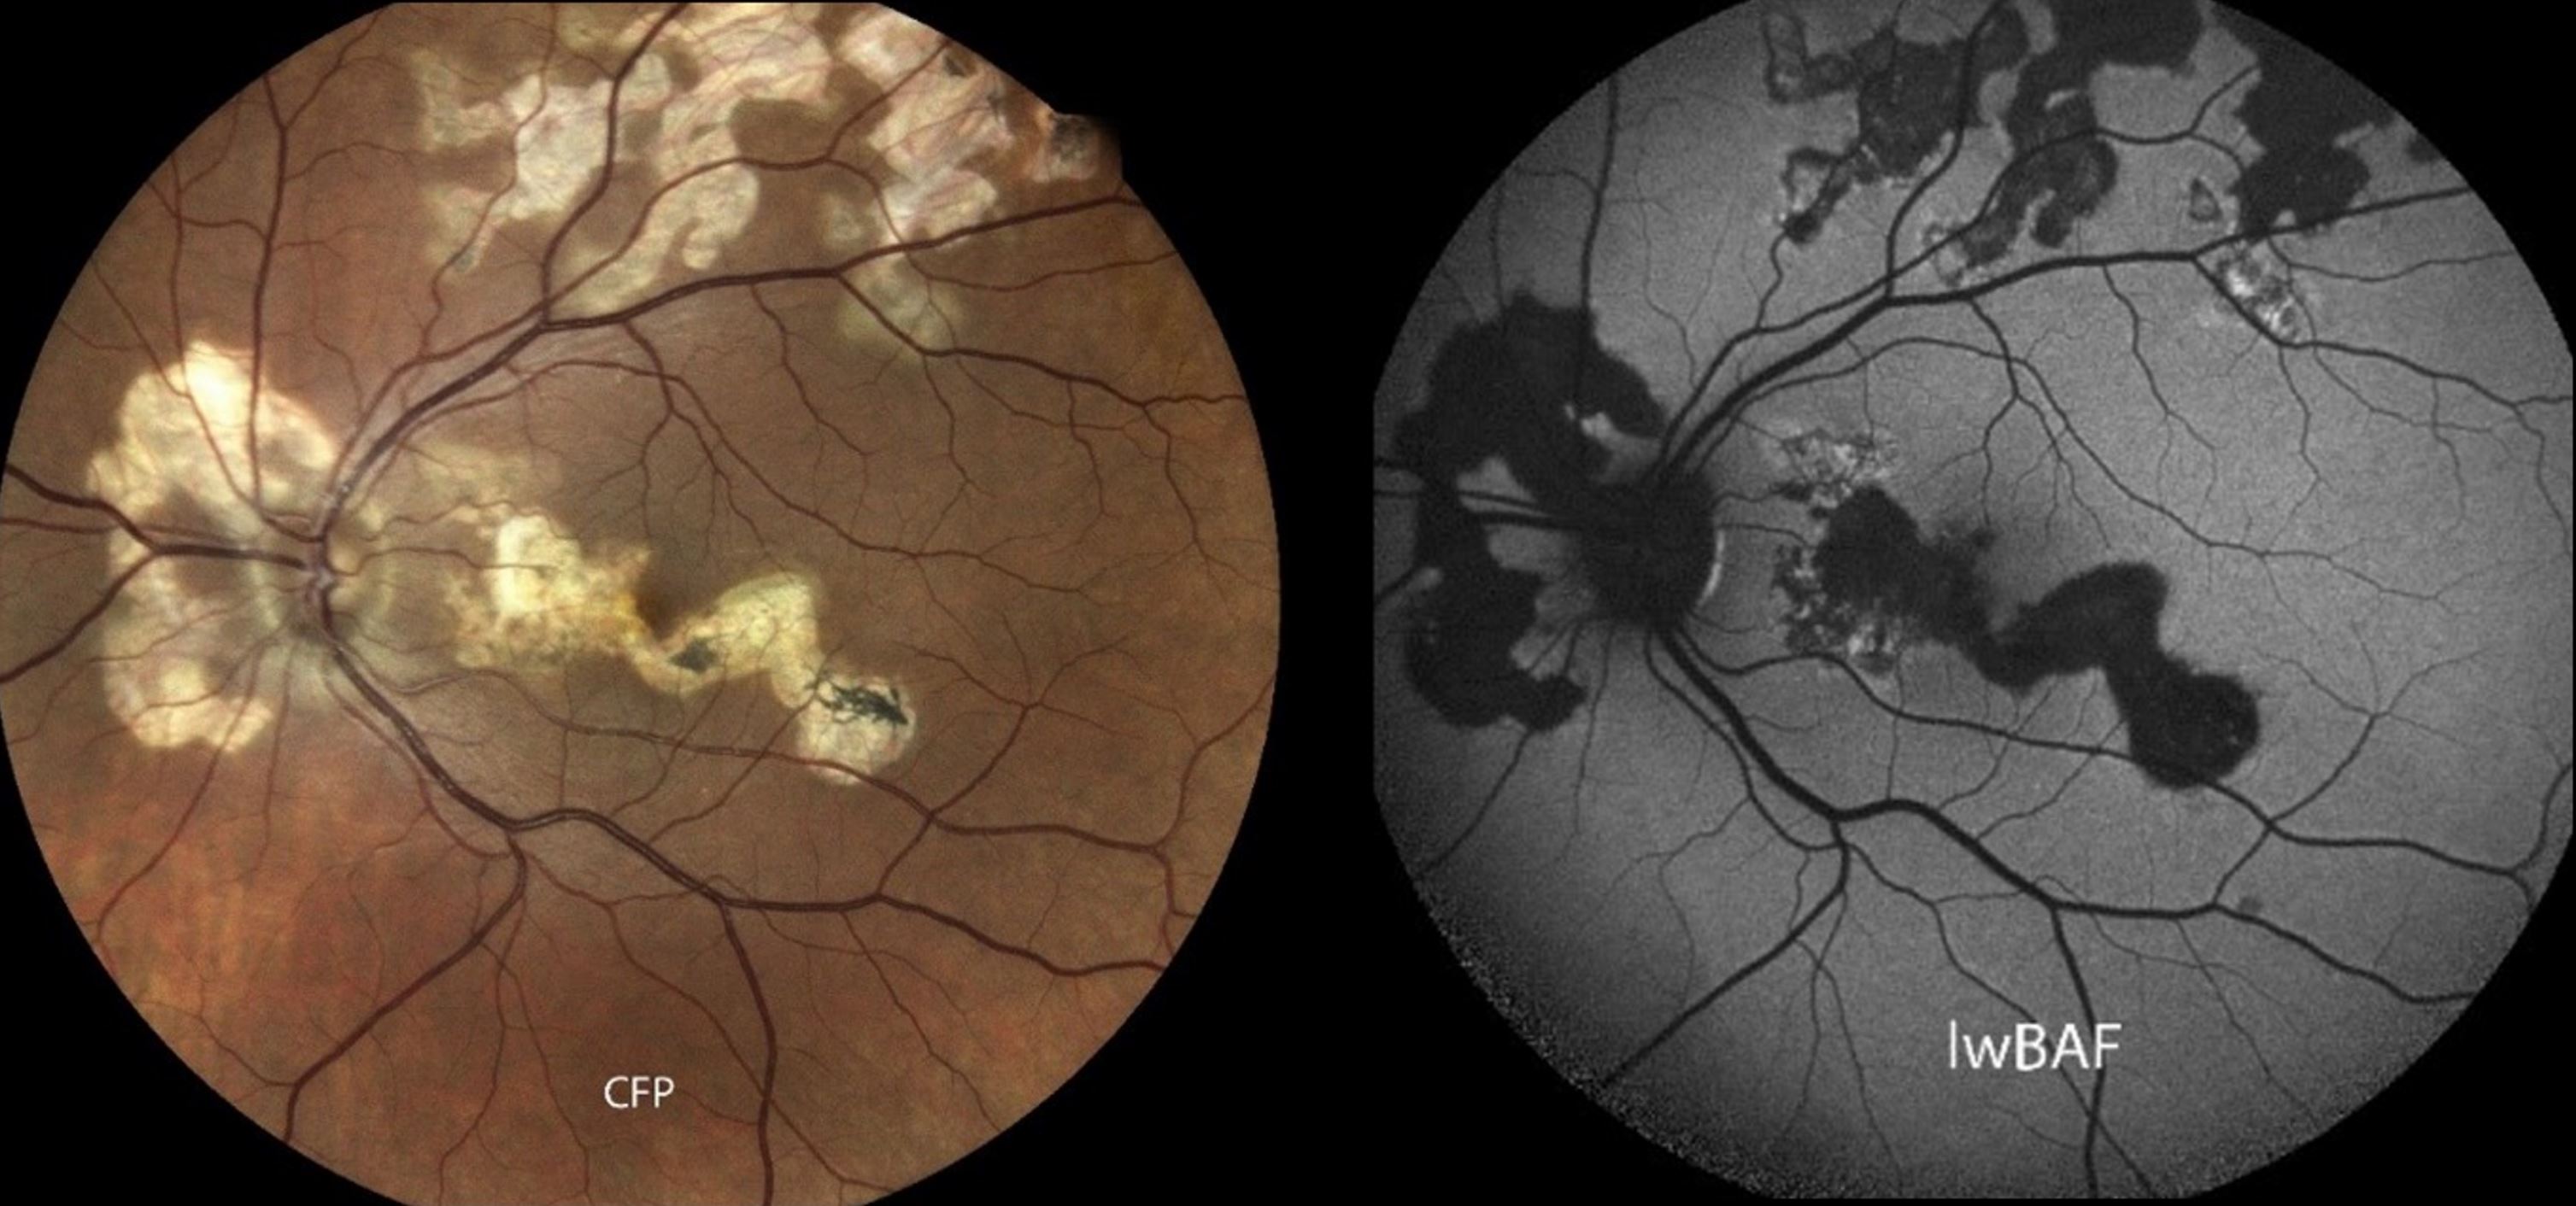

Die Fundusautofluoreszenz ist eine nicht-invasive Methode zur Bildgebung des Augenhintergrundes. „Durch Licht genau definierter Wellenlänge, werden sogenannte Fluorophore in den Gewebeschichten des Auges zum Leuchten angeregt. Die Verteilung dieser Fluorophore, die Intensität des Leuchtsignals sowie bestimmte entstehende Leuchtmuster können Rückschlüsse auf die zugrundeliegende Uveitis Form geben“, erklärt Wintergerst. In unklaren Fällen kann dies dabei helfen, die korrekte Diagnose zu stellen. „Darüber hinaus kann uns das Autofluoreszenzsignal bei bestimmten Uveitis-Formen auch Hinweise zum aktuellen Entzündungszustand liefern. So gehen stark leuchtende Bereiche in der Netzhaut teilweise mit aktiver Entzündung einher, während dunklere Bereiche Hinweise auf inaktive Entzündung sein können“, ergänzt Privatdozent Dr. Matthias Mauschitz, Leiter der Uveitis-Sprechstunde am UKB.

„Je nach benutzter Wellenlänge, kann sich das Autofluoreszenzsignal aus der Netz- und Aderhaut deutlich unterscheiden. So können abhängig von der Anregungswellenlänge Läsionen in unterschiedlichen Tiefen und damit verschiedene Bereiche abgebildet werden“, erklärt Mauschitz. Ergänzend zu ihrer Übersichtsarbeit haben die Forschenden eine Fallserie einbezogen, in der sie die Autofluoreszenz verschiedener Wellenlängen vergleichen. Es zeigt sich insgesamt, dass die Kombination verschiedener Wellenlängen zusätzliche Hinweise auf die zugrundeliegende Uveitis-Form geben kann.